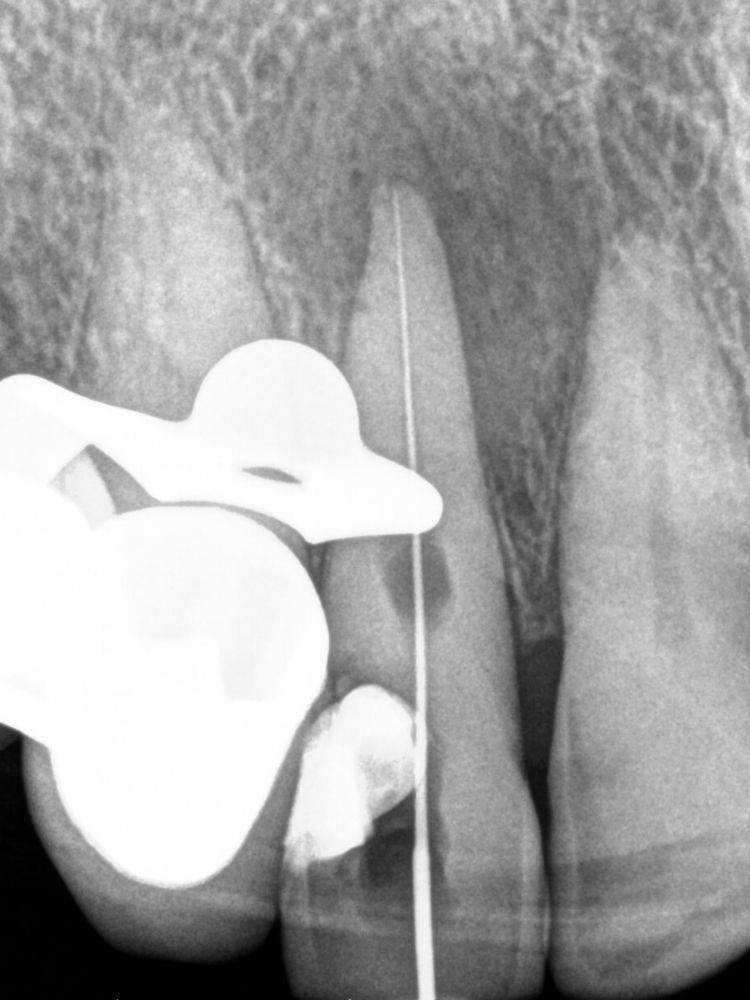

En una primera visita realizamos la instrumentación del conducto y la irrigación del mismo y de la cavidad de la reabsorción. Para mejorar el tratamiento del conducto se deja en su interior un material muy específico, denominado hidróxido de calcio.

En una segunda cita pasamos al siguiente peldaño del tratamiento. Procedimos a retirar todos los materiales intraconducto y obturar. Para ello, en primer lugar, se realiza el Downpack con System B para sellar el tercio apical. A continuación, con la técnica de inyección de gutapercha, se rellena el tercio medio y coronal del conducto de la pieza 1.2, con el consiguiente sellado de la cavidad de la reabsorción.